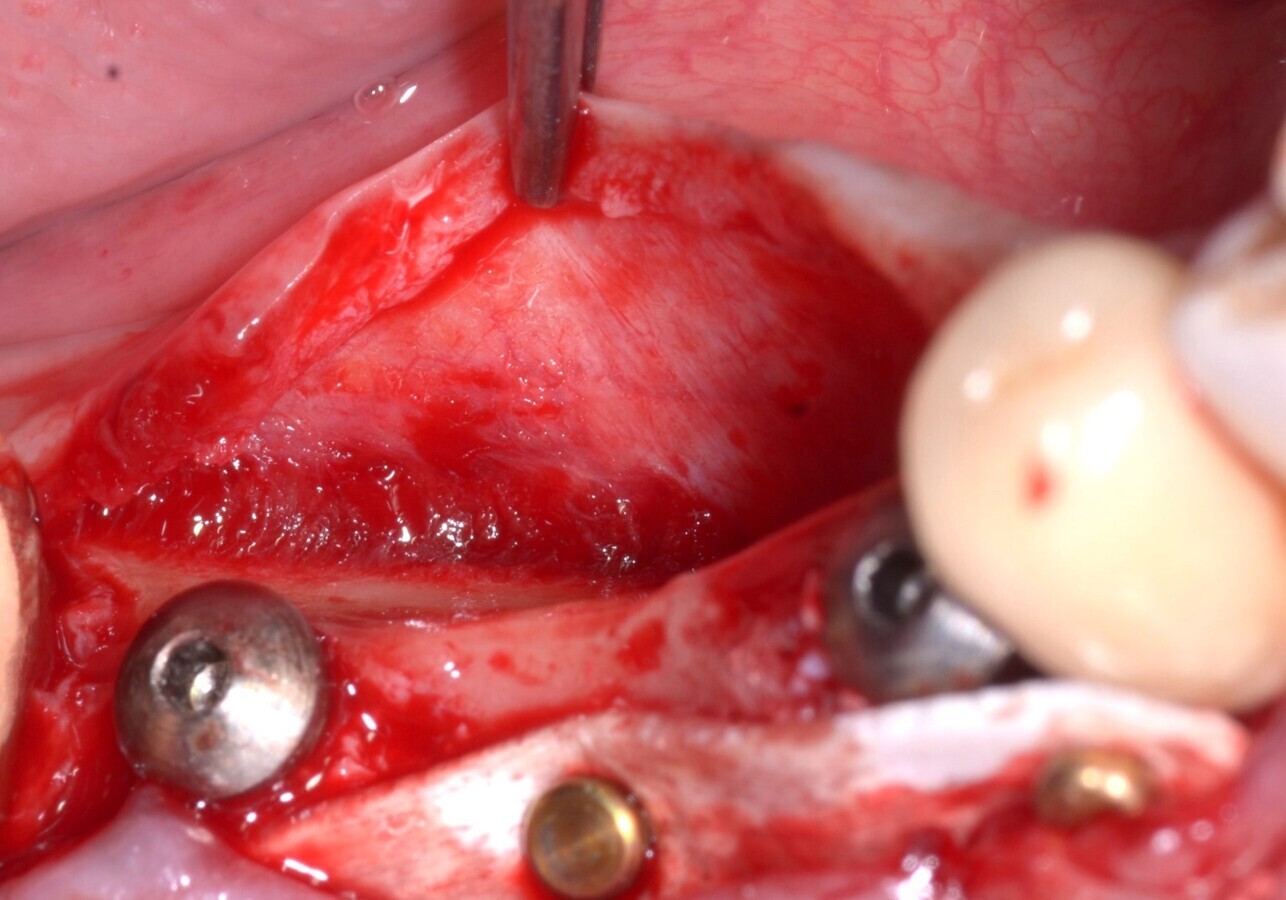

A los 4 meses de la ROG, el aspecto clínico mostraba una excelente cantidad de hueso recién formado y bien vascularizado (Fig. 10).

Fig. 10. Reapertura a los 4 meses que muestra la excelente cantidad de hueso recién formado y la buena vascularización del sitio, signo de hueso vital y maduro. El incremento horizontal es de 3 mm.

La lámina cortical se había remodelado completamente en hueso nuevo y se extrajeron los pernos que la habían inmovilizado. Se aplicaron tornillos de cicatrización para preparar el tejido blando (Fig. 11) para la prótesis definitiva. Dos meses más tarde se colocó un puente fijo de cerámica de 3 unidades, con los pilares 44 y 46 colocados.